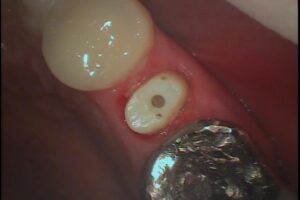

健康な歯の部分を歯肉の上に引っ張り出して、その根の治療、土台を作り、硬いセラミックで歯を覆い、歯を温存する治療方法です。

全ての歯に適応できるわけでは無いですが、奥歯の大きい救歯には救歯セラミックといった、BTAテクニック®を応用した方法で歯を抜かずに温存する方法を適応できる場合があります。